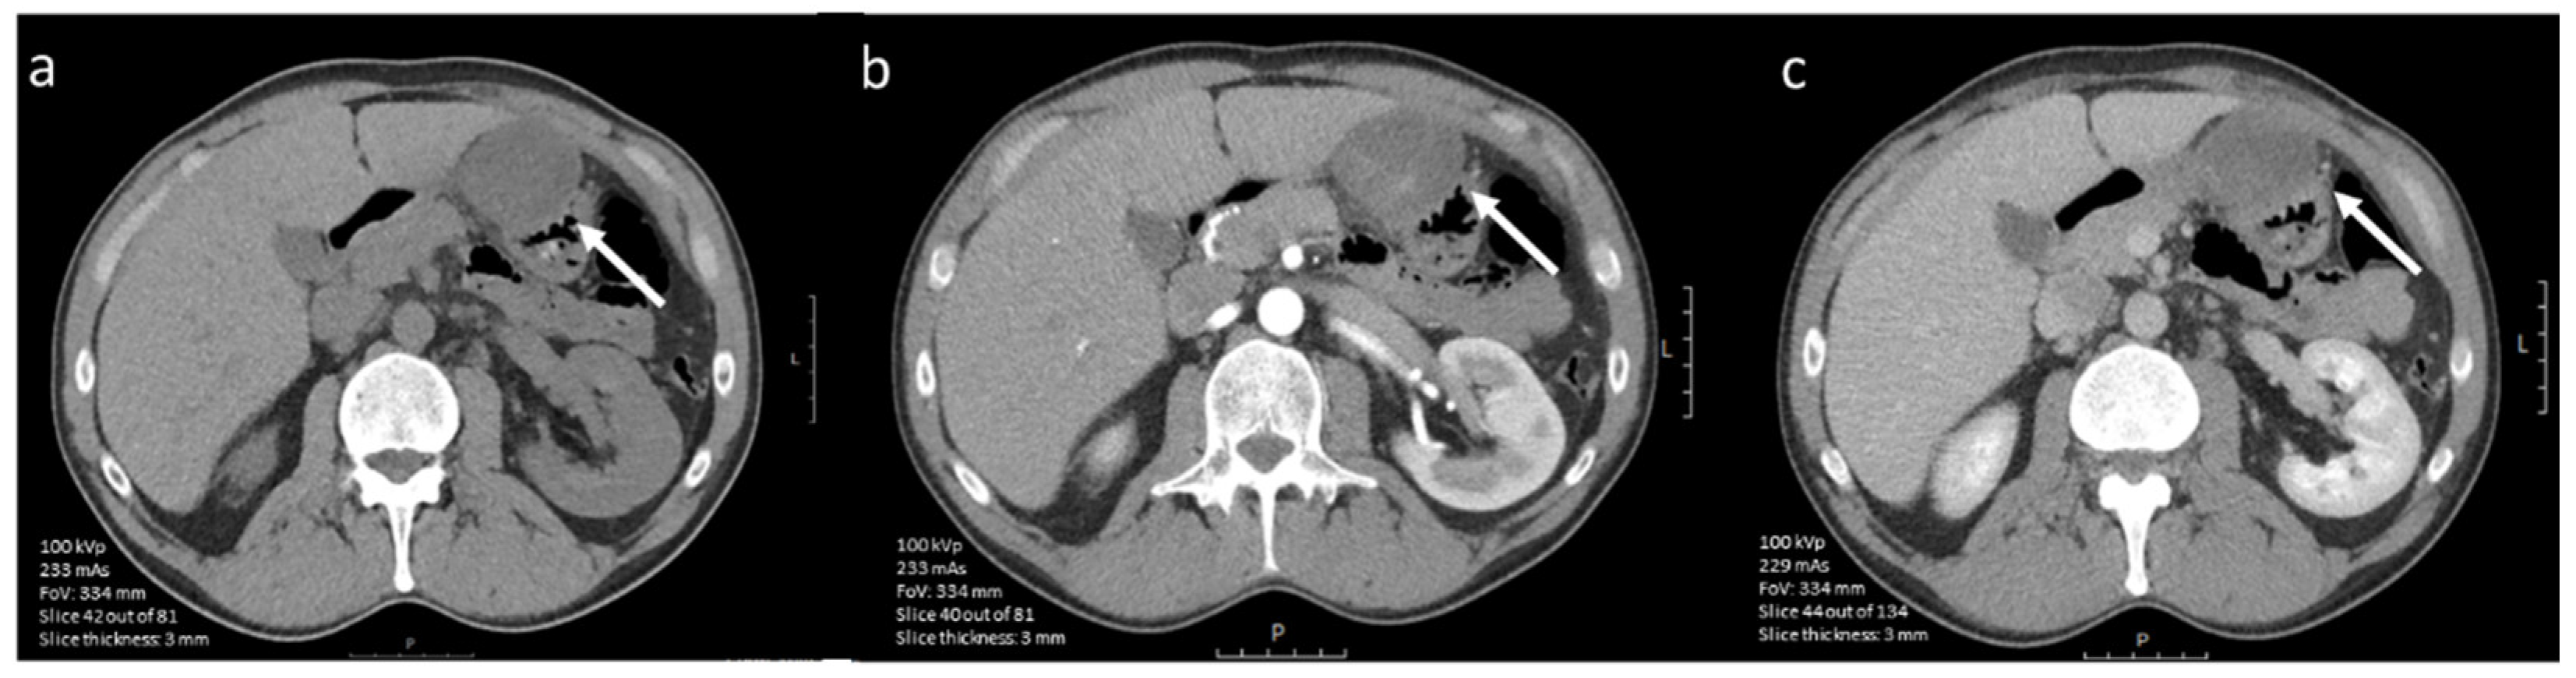

3.4.1. CE-CT Imaging